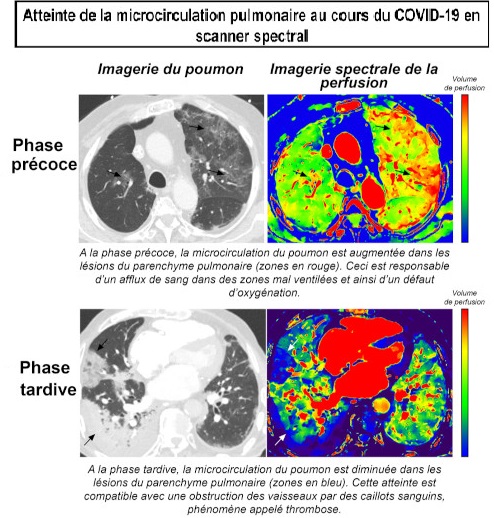

La TDM spectrale , c'est la technique qui consiste à

utiliser différentes énergies du rayon X pour

obtenir des images caractéristiques des tissus

et ce qu'il peut d'explorer

l’implication sur le système

vasculaire pulmonaire

par la perfusion et d'analyse

des modifications de la perfusion du systeme vasculaire

pulmonaire à

différents stades de l’affection